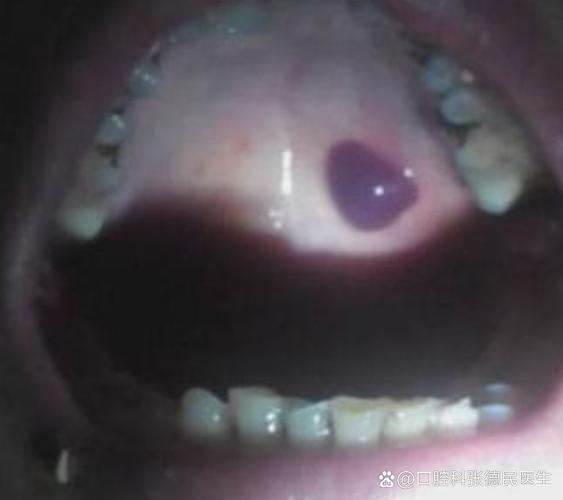

口腔内壁黑血泡是艾滋症状吗? 请不要过度恐慌,我们来科学、客观地分析一下这个问题。(图片来源网络,侵删) 核心观点:口腔内壁黑血泡与艾滋病没有直接的必然联系。 绝大多数情况下,口腔内的黑血泡是由其他更常见、更良性的原因引起的,艾滋病病毒(HIV)感染后,口腔出现的症状通常是特定的、并且是晚期的表现,而不是一个孤立的、突然出现的黑...